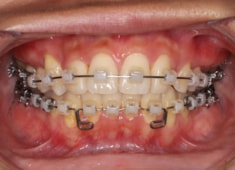

治療開始時